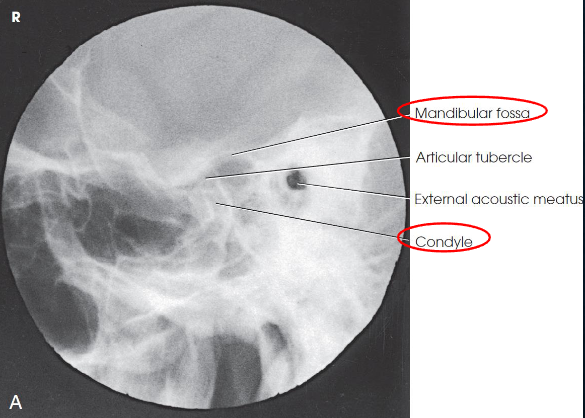

Axiolateral (modified Schuller) TMJs image criteria

TMJ with mouth open and closed

both sides done for comparison

TMJ anterior to EAM

closed mouth: condyle in mandibular fossa

open mouth: condule inferior to the articular tubercle